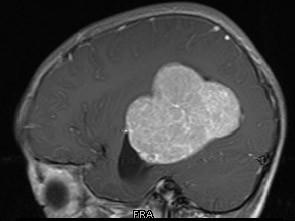

问题 男,8岁,头痛伴呕吐,左侧眼视物不适5天,请根据所提供图像,选择最可能的诊断()

选项 A.(左侧脑室)脑膜瘤 B.(左侧脑室)室管膜瘤 C.(左侧脑室)脉络丛乳头状瘤 D.(左侧脑室)胶质瘤 E.(左侧脑室)少突胶质细胞瘤

答案 C